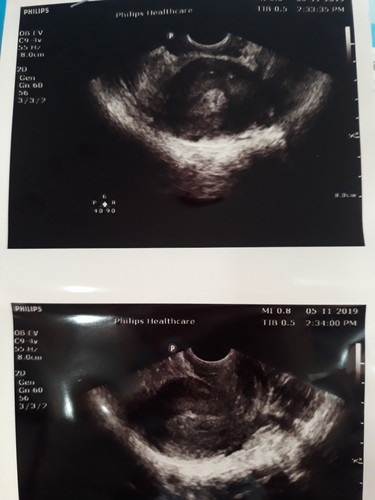

หมอซาวแล้วเห็นแค่นี้เด็กยังอยู่มั้ยค่ะ

หมอซาวแล้วเห็นแค่นี้ตกลงเด็กยังอยู่มั้ยค่ะ

หมอบอกรออีก1อาทิตให้ไปซาวใหม่ค่ะขอบคุณสำหรับความคิดเห็นค่ะ